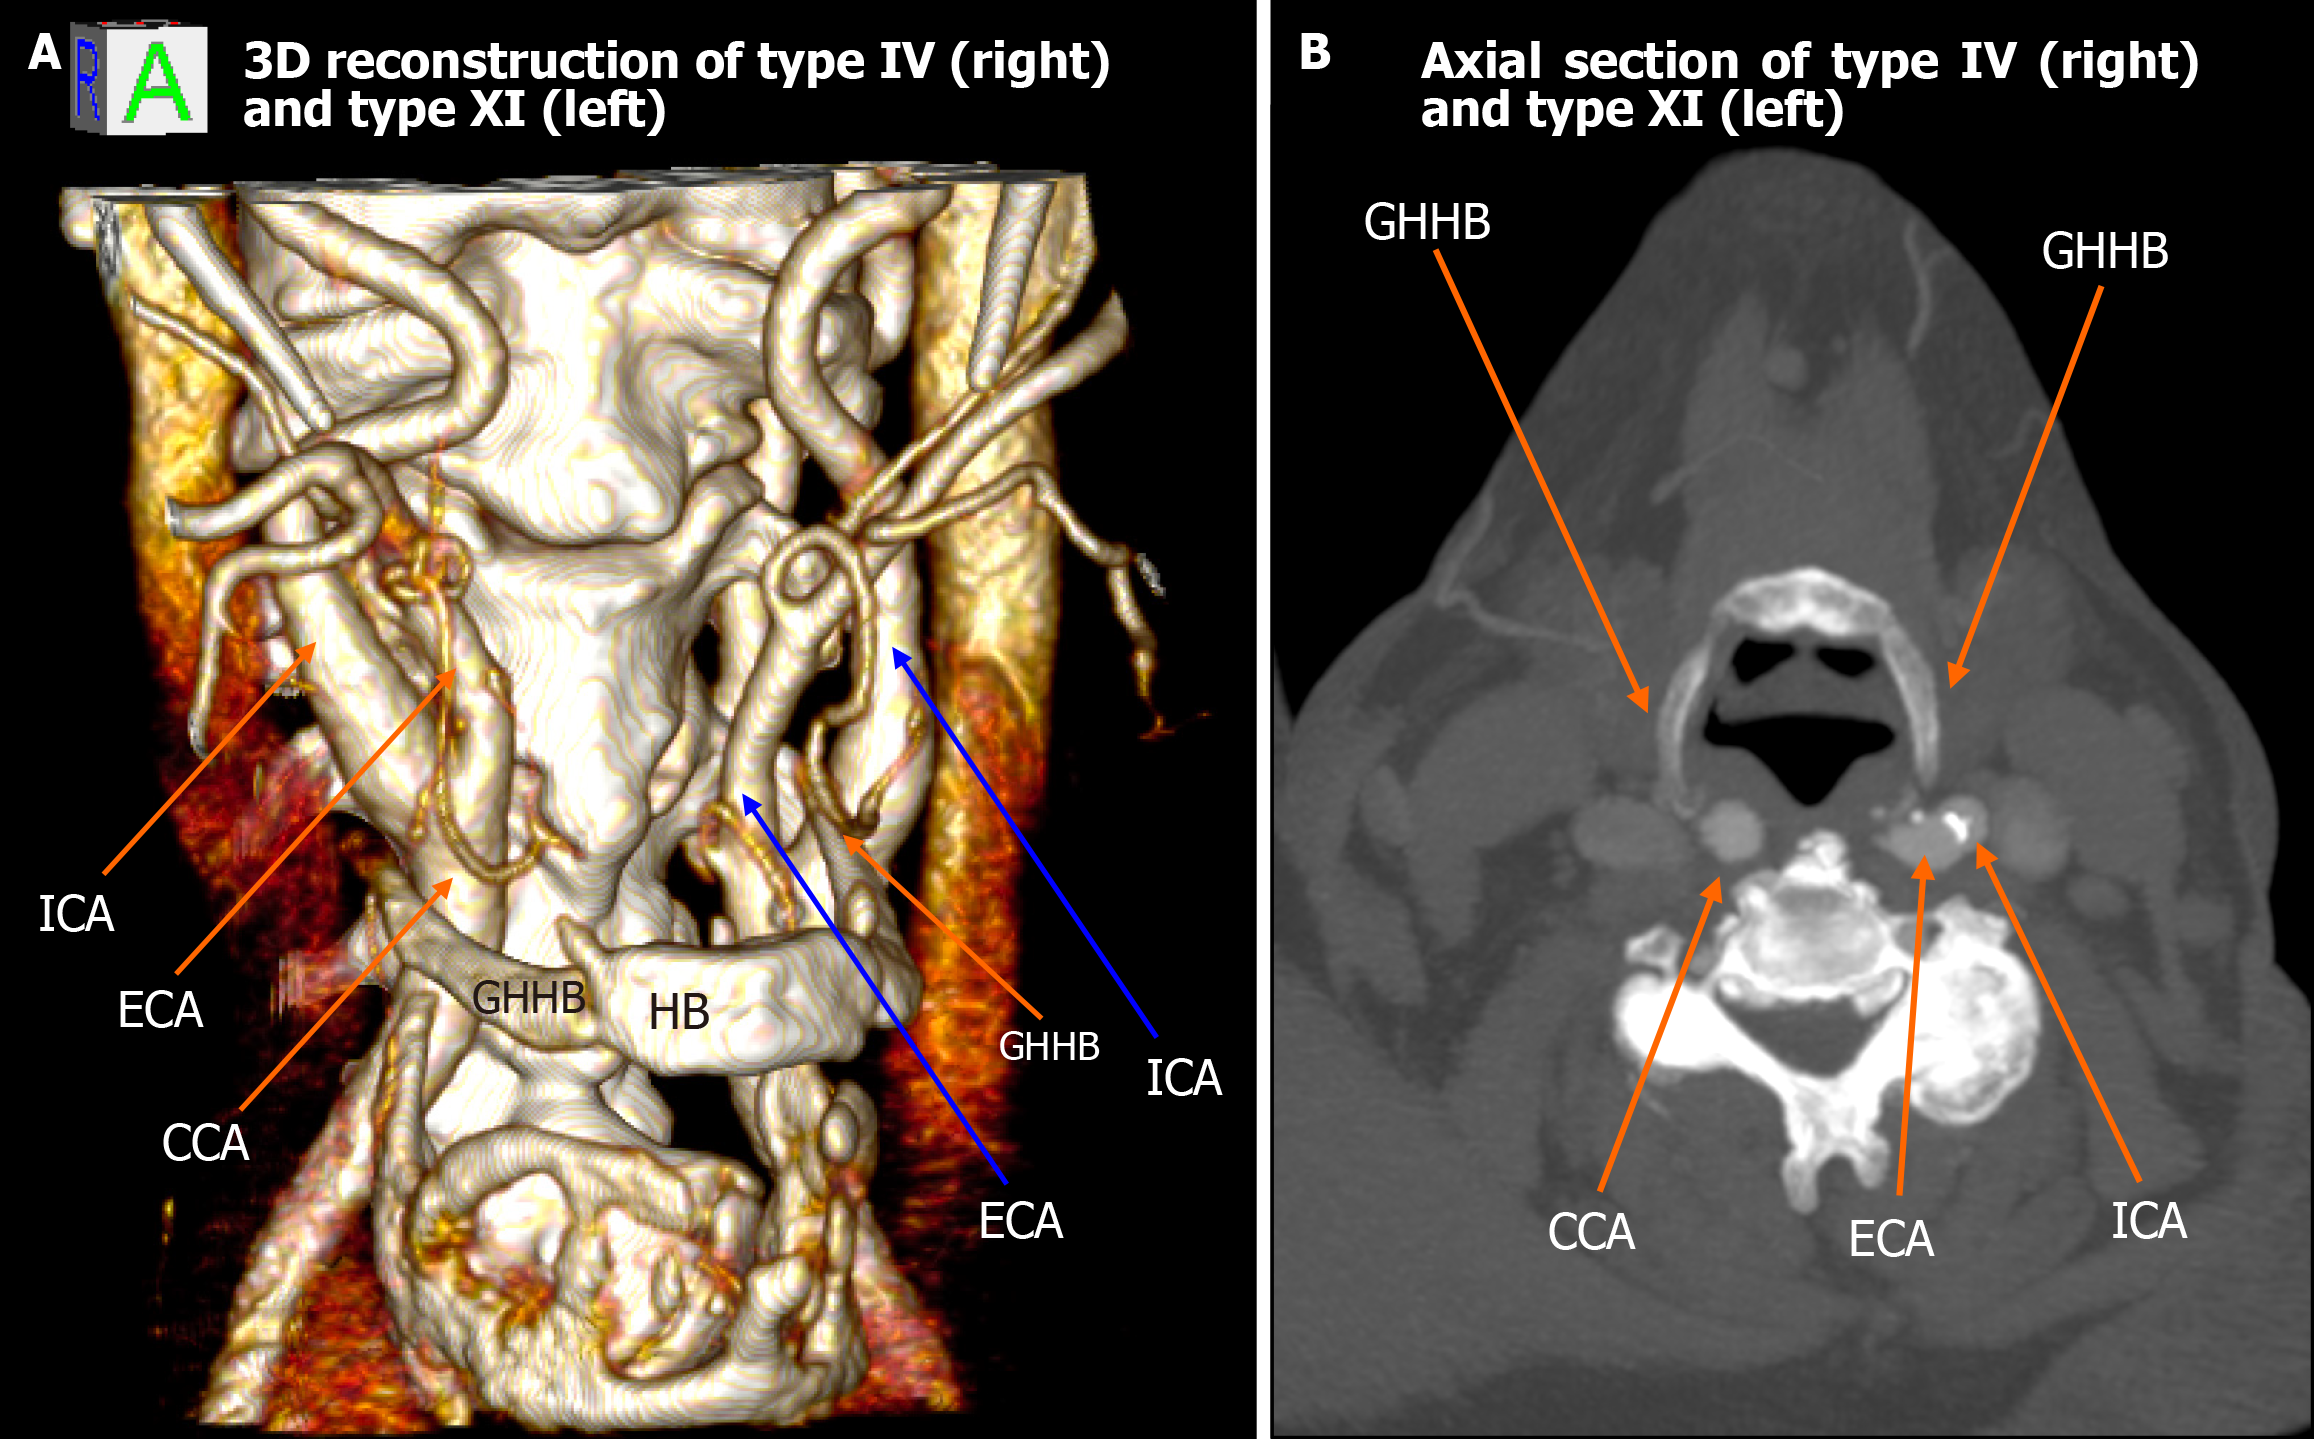

Figure 2 Type IV (right) and type XI (left) configuration.

A: 3D reconstruction shows the right common carotid artery positioned medial to the greater horn of hyoid bone (type IV) and the left external carotid artery lateral with internal carotid artery medial to greater horn of hyoid bone (type XI); B: Axial computed tomography images confirm the asymmetric carotid-hyoid relationships. ICA: Internal carotid artery; ECA: External carotid artery; CCA: Common carotid artery; GHHB: Greater horn of hyoid bone; HB: Hyoid bone.